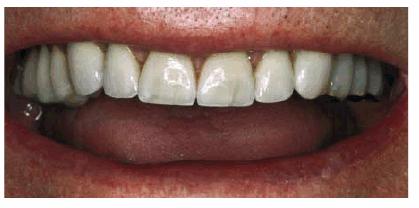

fracture the bonding, then porcelain would be a better alternative (Figur 323s1823d es 18-3A 18-3B 18-3C 18-3D 18-3E and F). In the event that the enamel is

Figur 323s1823d e 18-3A: This young lady fractured her maxillary anterior incisors. Despite numerous bonding repairs, she continued to refracture the teeth. Because she also objected to the incisal translucency, she was treatment planned for three porcelain laminates.

Figur 323s1823d e 18-3E and F: Three porcelain laminates were placed on the central incisors and right lateral. The new laminates also achieved the objective to eliminate the incisal translucency.